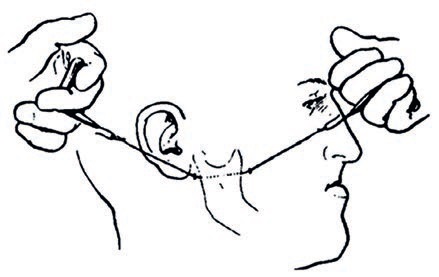

W trakcie przeprowadzania leczenia endodontycznego lekarz może napotkać trudne do przewidzenia problemy, które mogą prowadzić do powikłań w leczeniu. Jednym z takich powikłań jest perforacja – przypadkowe wykonanie połączenia między jamą zęba a ozębną. Perforacje stanowią drugą najczęstszą przyczynę niepowodzeń endodontycznych [5].

Podstawowe powody powstawania perforacji to:

- brak odpowiedniego dostępu koronowego,

- zaniechanie doginania narzędzi, szczególnie tych z tnącym wierzchołkiem,

- zbyt szybkie używanie dużych rozmiarów narzędzi docierających na długość roboczą,

- praca bez zastosowania narzędzi powiększających (mikroskop, lupa) [2].

Wg Arabskiej-Przedpełskiej wyróżniamy perforacje: korony, środkowego odcinka korzenia, dna komory, korzenia w okolicy wierzchołkowej. Ponadto niektórzy autorzy wyróżniają perforacje 1/3 koronowej części korzenia i w okolicy furkacji – typu stripping-strip perforation [4].